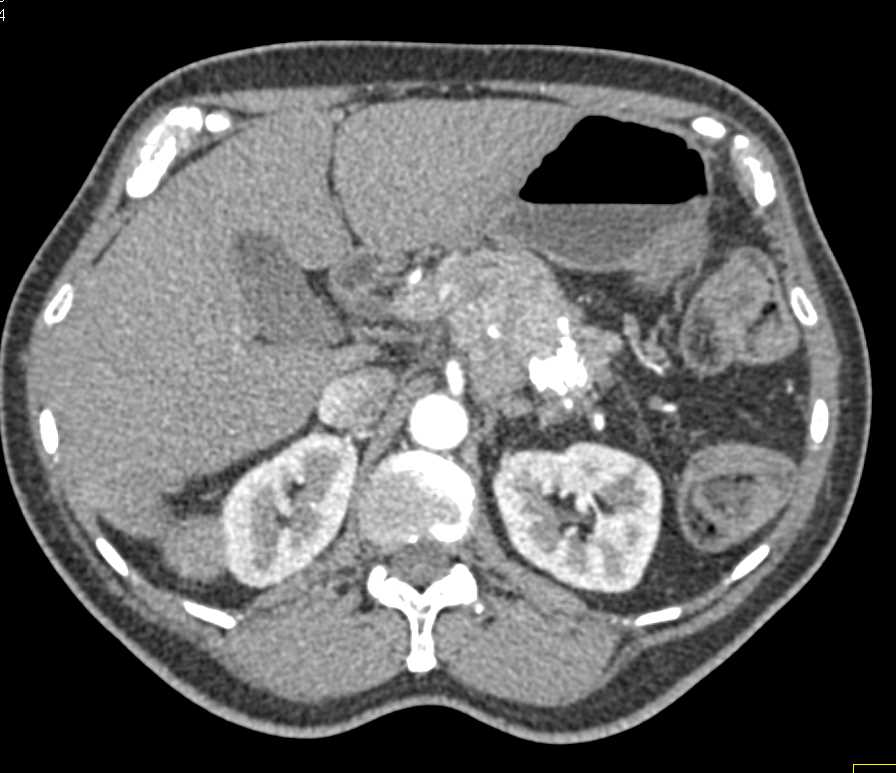

Neuroendocrine Tumor Pancreas